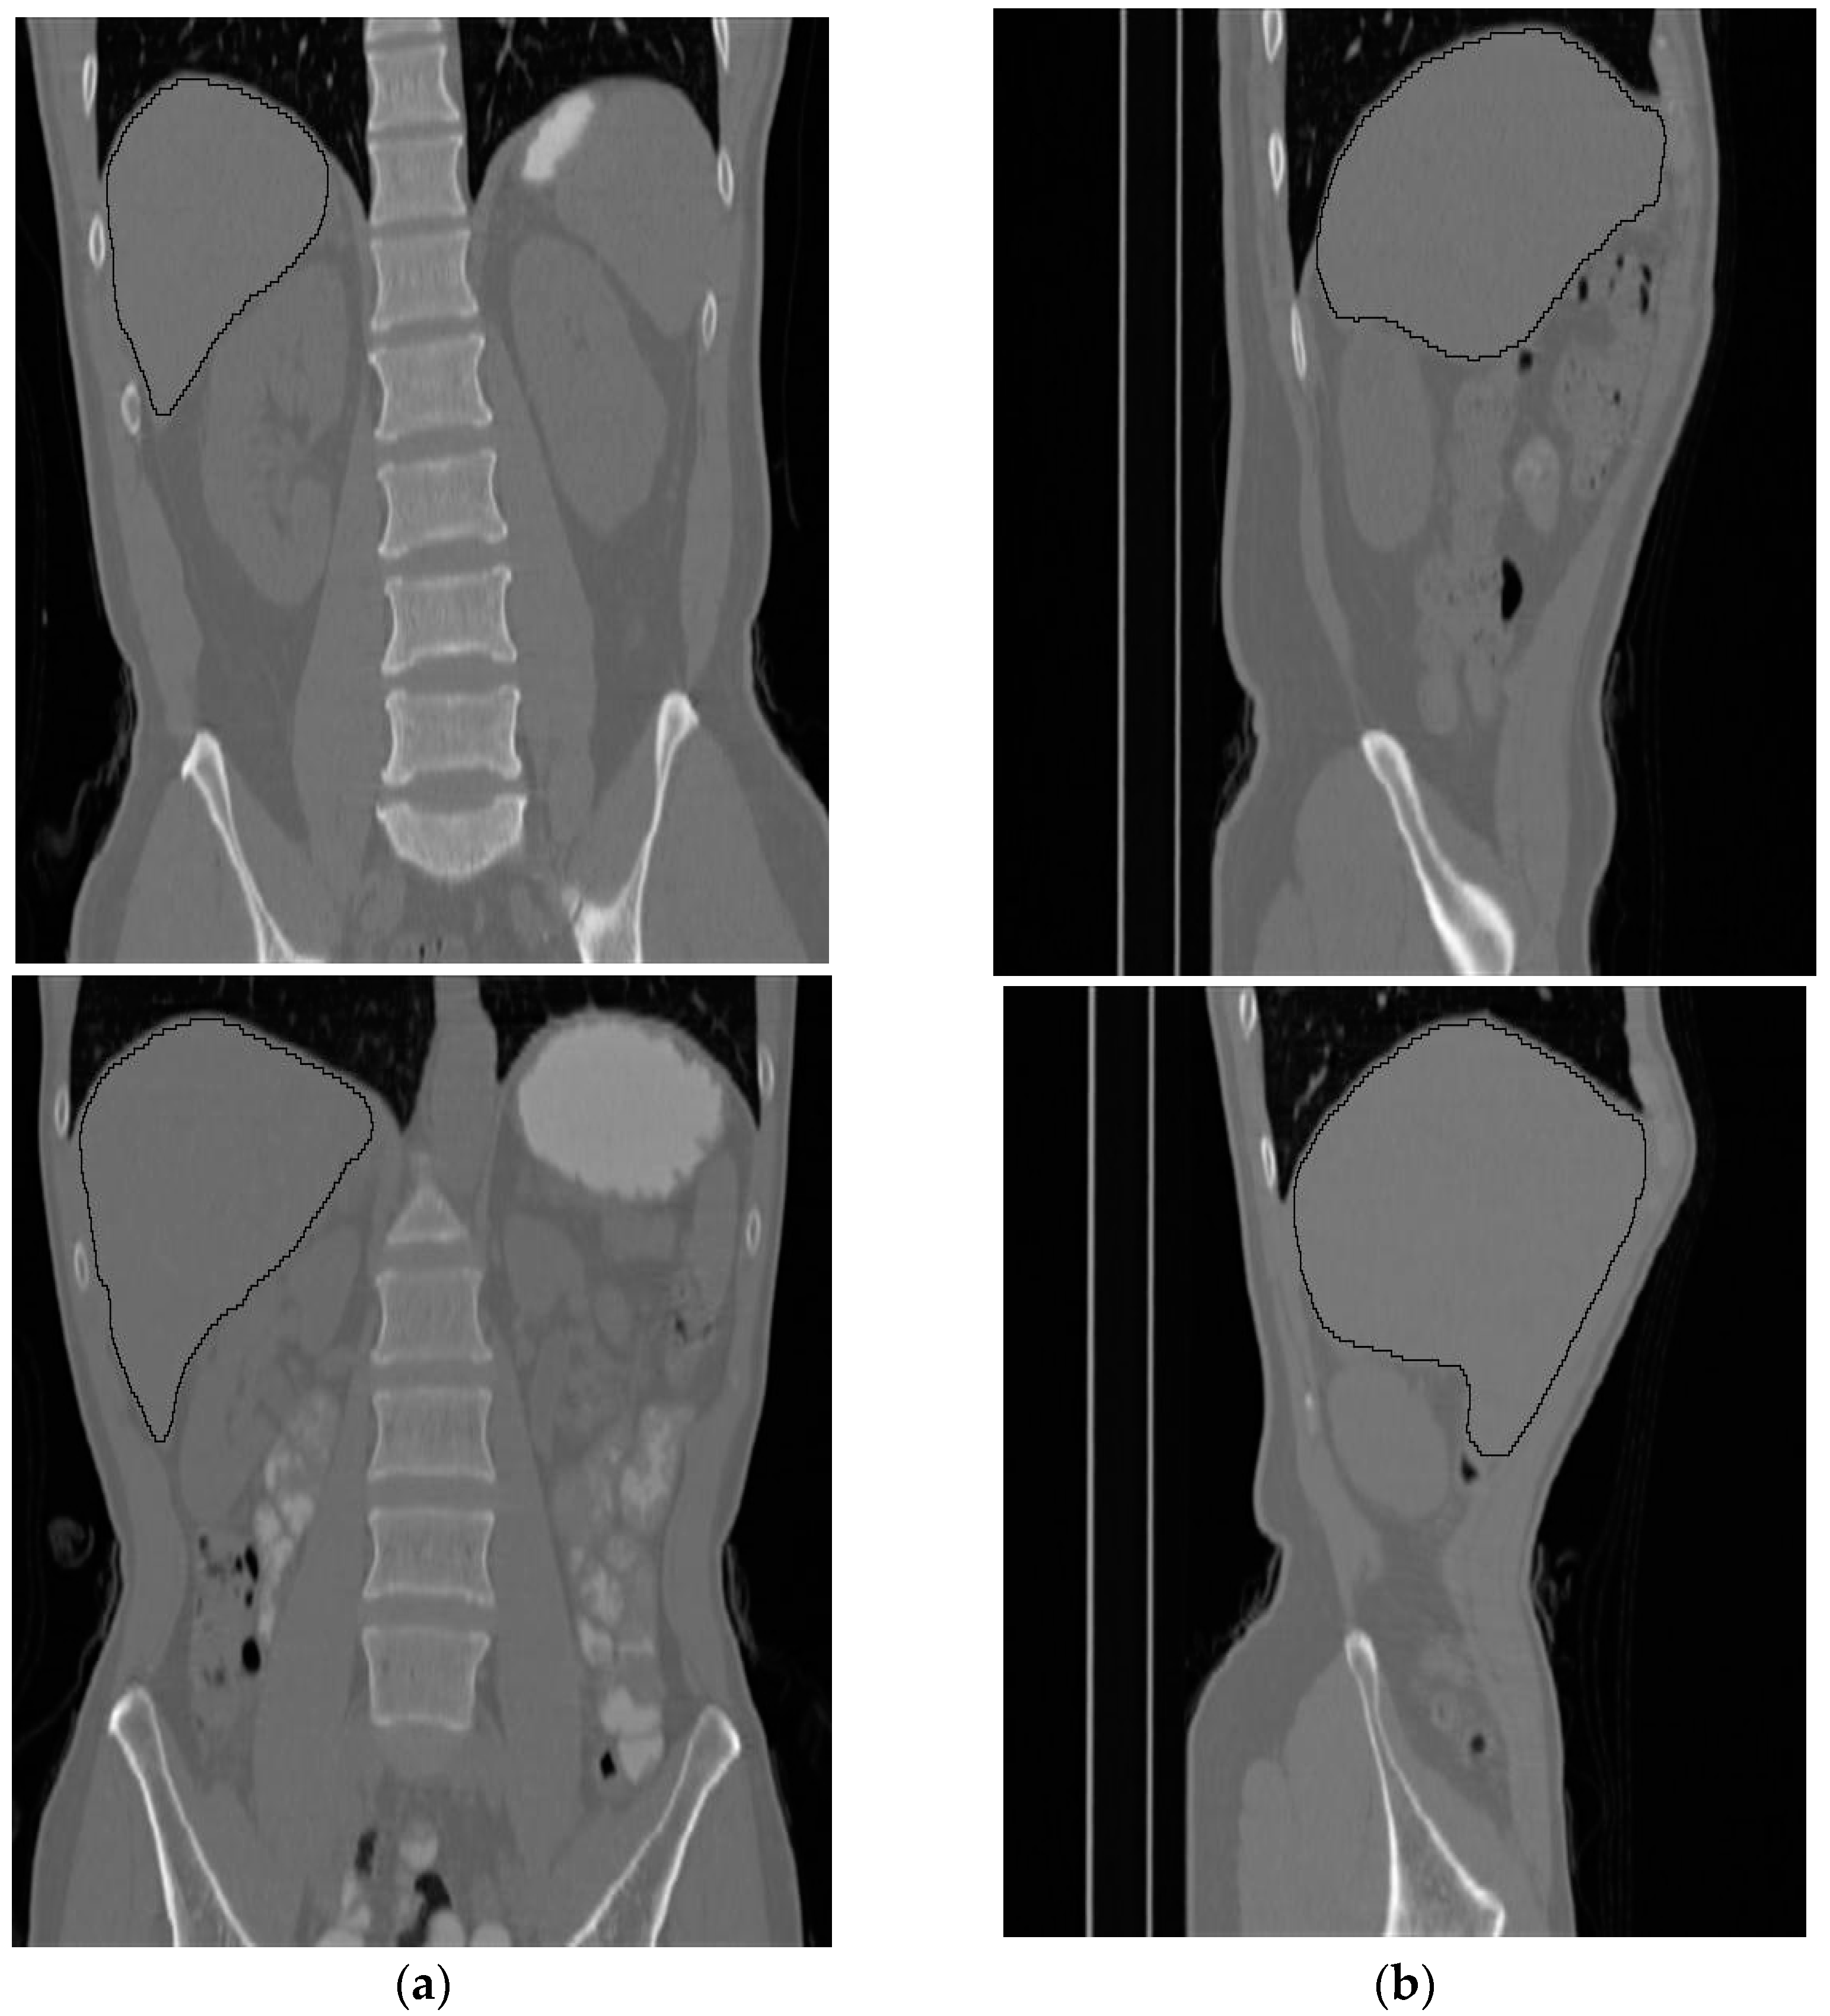

Figure 11 shows side and front views for two subjects where the liver is bounded by black contours.

Figure 11.

Two samples of the results of the liver segmentation method. (a) Front view, (b) side view.

The volumetric information for the total abdomen fat, SF, and VF does not provide realistic information about obesity due to the variation in the sizes of people. Therefore, the following ratios were used as an indication of obesity. For each subject, CT slices between the first and fifth lumbar vertebrae (L1–L5) were used. Figure 12 shows two samples that highlight the area where the CT slices were selected from. The region of interest is bounded by the two white lines.

Figure 12.

Two samples show the area where the CT slices are selected from. (a) Front view, (b) side view.